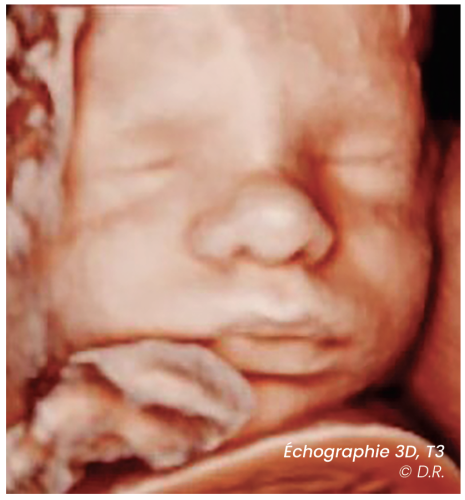

Les discussions qui s’ensuivent parfois, autour du DPNI ou de l’amniocentèse bousculent les patientes. Elles prennent conscience soudain que le ciel n’est pas toujours tout bleu. L’échographie du deuxième trimestre, est la plus complète. C’est là qu’on voit le cœur, le cerveau, les organes du bébé, le placenta, on évalue la croissance…

Celle du troisième trimestre peut être vue comme un complément de la deuxième, mais ce sont les mêmes vérifications qui sont refaites, et l’accent est mis sur l’accouchement (position fœtale, estimation de poids, placenta).